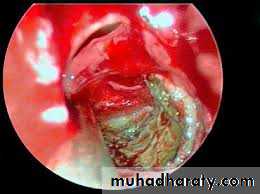

• Mycetoma(Fungal ball). These are masses of fungal debris that usually occur in the maxillary or ethmoid sinuses. Patients are typically immunocompetent and non-atopic. Aspergillus fumigatus is the most common organism isolated. Treatment is by endoscopic removal of debris and ventilation of the sinus. There is usually no requirement for antifungal or any other systemic therapy.26

Mycetoma